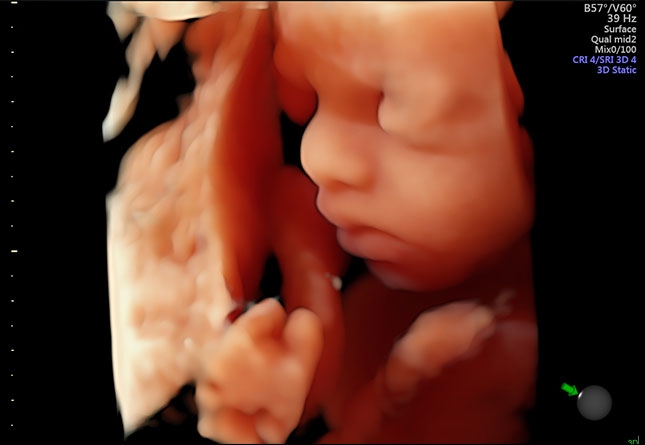

УЗИ аппарат Voluson S10 позволяет проводить обследования высочайшего уровня с максимальной точностью диагностики. Благодаря технологии Voluson Core Architecture достигнут высокий уровень качества изображений с возможностью последующей обработки и анализа даже после проведения скрининга. Технология HDlive делает изображения удивительно реалистичными и объемными.

• HDlive в 3D и 4D - режим перемещаемого виртуального источника освещения - "виртуальная фетоскопия"